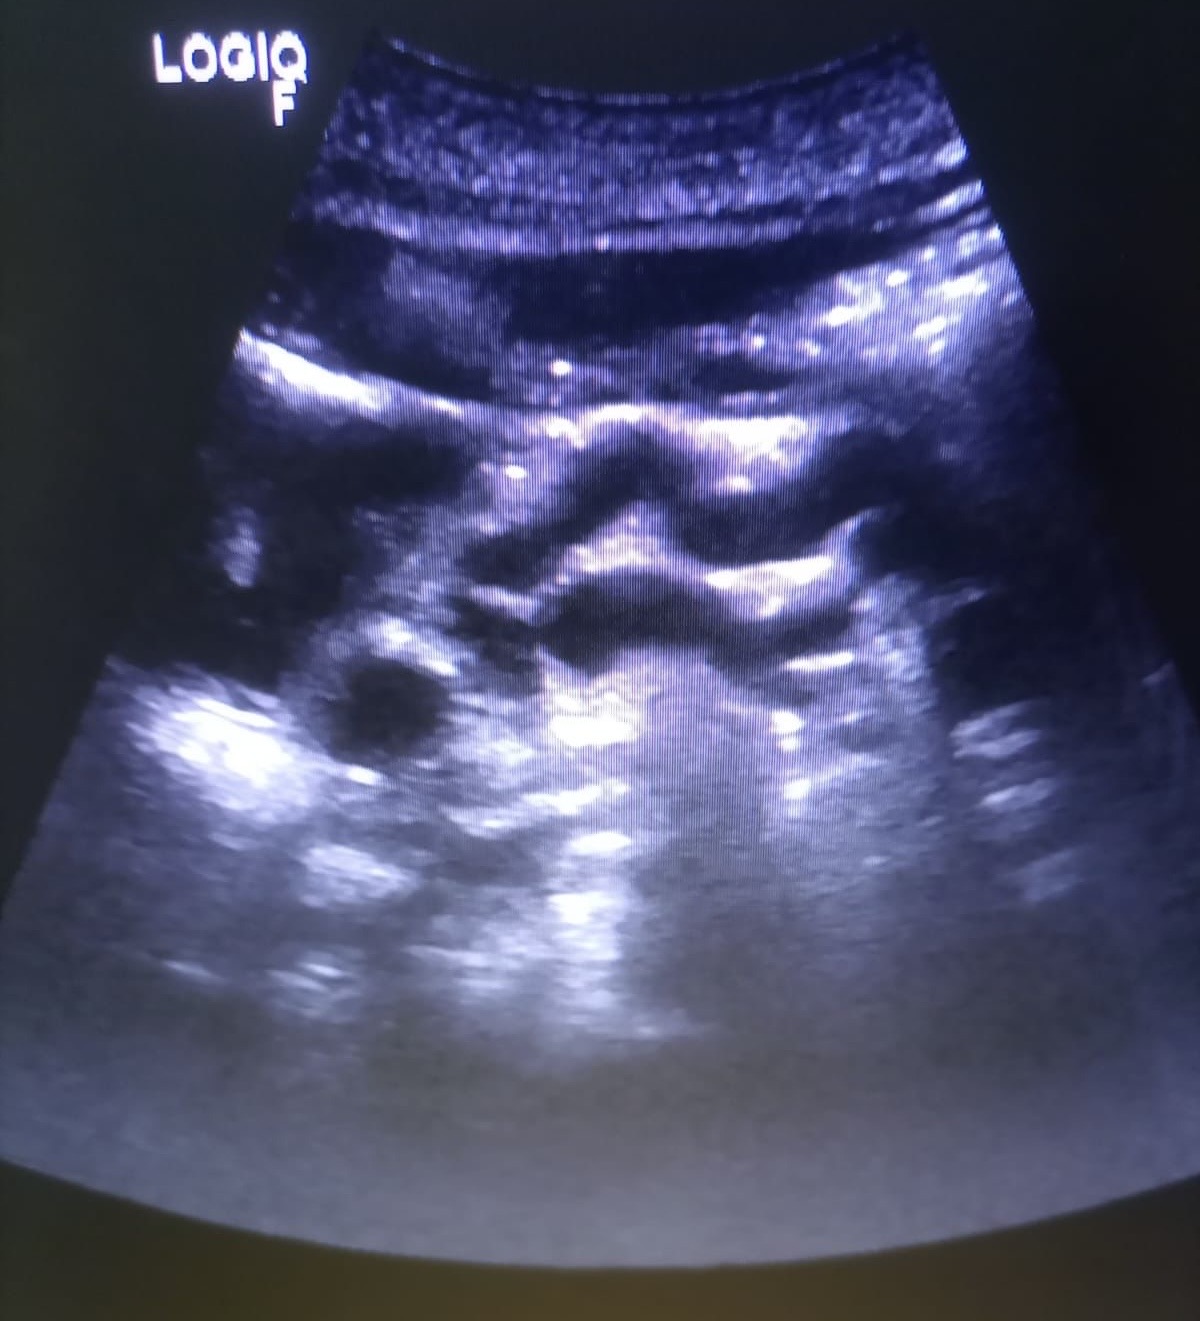

Hallazgos ecográficos

Observamos una lesión a nivel de la cabeza del páncreas, de bordes mal definidos, hipoecogénica, además de dilatación del conducto de Wirsung y dilatación de la vía biliar tanto intra como extrahepática.